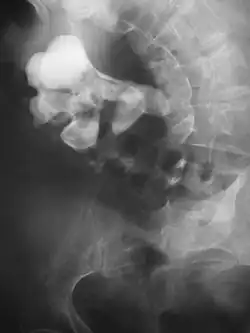

Calcium-containing stones are relatively radiodense (opaque to X-rays), and they can often be detected by a traditional radiography of the abdomen that includes the kidneys, ureters, and bladder (KUB film).[59] KUB radiography, although useful in monitoring size of stone or passage of stone in stone formers, might not be useful in the acute setting due to low sensitivity.[60] Some 60% of all renal stones are radiopaque.[61][62] In general, calcium phosphate stones have the greatest density, followed by calcium oxalate and magnesium ammonium phosphate stones. Cystine calculi are only faintly radiodense, while uric acid stones are usually entirely radiolucent.[63]

-

Bilateral kidney stones can be seen on this KUB radiograph. There are phleboliths in the pelvis, which can be misinterpreted as bladder stones. -